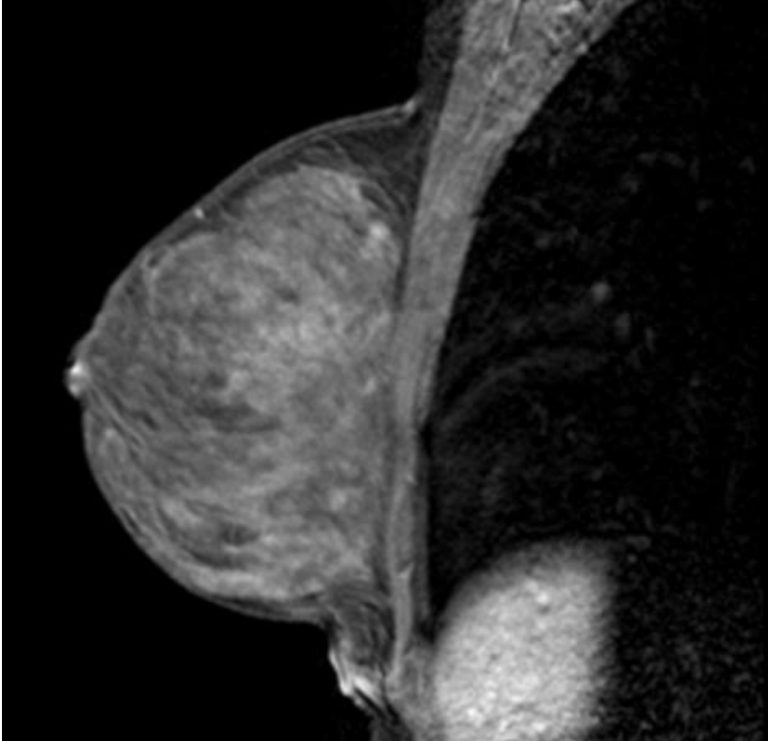

Ultrasonografía.

El ultrasonido mamario es un examen no invasivo que utiliza ondas sonoras para crear imágenes de las estructuras internas del seno, ayudando en la detección de anormalidades como quistes y tumores. Esta indicado cuando la mujer es menor de 40 años o bien como estudio complementario a la mastografía.

Resonancia Magnética